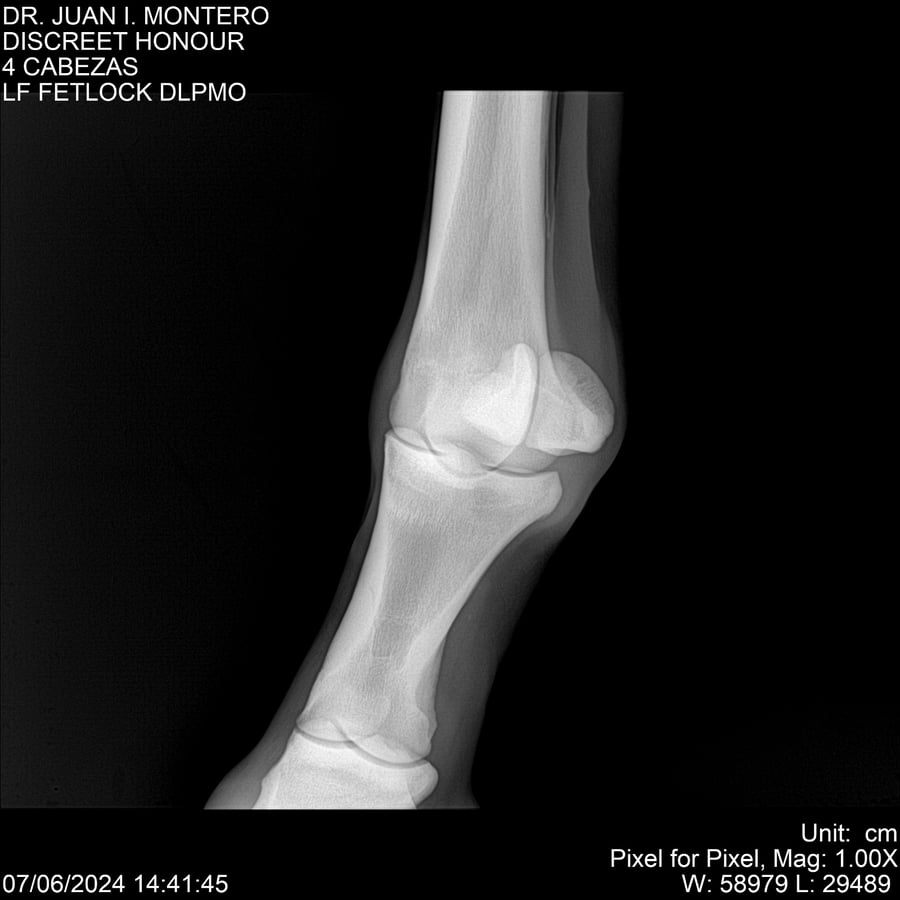

LOTE 6, DISCREET HONOUR 🔥 🔥 🔥 Lote Anterior Volver al remate Lote Siguiente Ficha Contacto Montevideo - Ficha del Lote Identificador: #281093 Categoría: Yeguarizos Montevideo - 82 Visualizaciones ClicData Contacto Empresa: Abelenda N. R., Walter Hugo Nombre*: Teléfono* : E-mail* : Mensaje Enviar Registrese gratis Este contenido Exclusivo está disponible sólo para usuarios registrados Ingresar